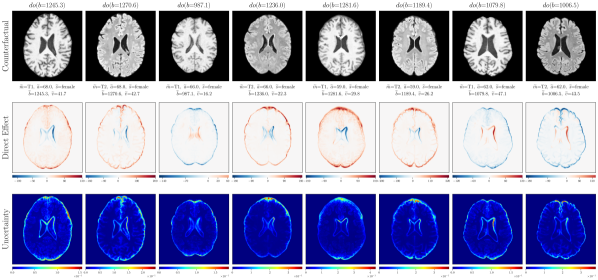

4.3 Chest X-ray Imaging Counterfactuals

We further extend the proposed approach to the MIMIC-CXR dataset (Johnson et al., 2019) to demonstrate our model’s ability to estimate high-fidelity counterfactuals of real chest X-ray images. This is motivated by the need for a better understanding of algorithmic bias and reported subgroup disparities (Bernhardt et al., 2022). We begin with an assumed causal generative process of data involving the following observed variables: age (), sex (), race (), disease (), and chest X-ray image (). Notably, we assume that age causes disease (pleural effusion) which requires inference of discrete counterfactuals from upstream interventions on age. For details on computing discrete counterfactuals and other experiments, please refer to Appendix E. Following the general setup in Section 4.2, we used a scaled-up version of our exogenous prior HVAE for ’s mechanism. We trained for relatively few iterations on MIMIC-CXR; K. The quantitative counterfactual evaluation results from random interventions on each variable are reported in Table 2. We observed significant improvements in counterfactual effectiveness post counterfactual training, particularly for race, age and disease attributes. For extensive visual evaluation results please refer to Appendix E.4.

E.4 Extra results

‘Sex’ counterfactuals

Post counterfactual training:

‘Race’ counterfactuals

‘Age’ counterfactuals

‘Disease’ counterfactuals

Null-Interventions on full SCM